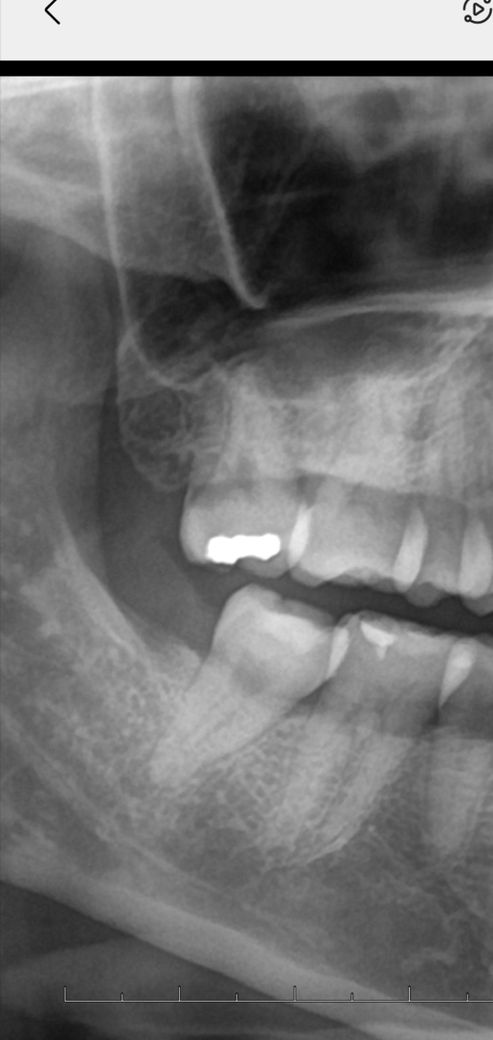

30대후반 치경부충치 깊은건가요?

안녕하세요 위끝어금니 치경부충치가있다고하는데 하나도안아파요..치석제거하니 분홍? 붉은충치인가사진상 그렇고 실제로는 잘모르겠어요 이거 전체파노라전체중 확대한건데 깊은충치로보이시나요 아니면 파봐야지 알수있는걸까요..

사진으로 봤을 경우 치경부에 어두운 부분이 보이기는 합니다. 하지만 해당부위는 구강내 연조직등이 겹치는 부분이라 방사선 사진으로만 어두운 경우도 있습니다.

충치여부를 확인하기 위해서는 육안적이나 촉진검사등이 추가적으로 필요할것으로 보입니다.

엑스레이 상으로는 충치가 깊어 보이진 않습니다만 실제로 충치를 제거하면 충치가 깊은경우가 잇습니다.

파노사진 봐서도 꽤 깊은 치경부 우식같습니다 충치에 대한 증상은 원래 케바케입니다 갑자기 아파지기도 하고요